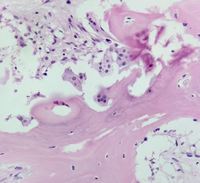

Osteoblast rimming

Category: Red Cell: Other Disorders > Bone/metabolic disease > Anemia of renal osteodystrophy

61yr old lady, a known case of chronic kidney disease, presenting with pancytopenia.